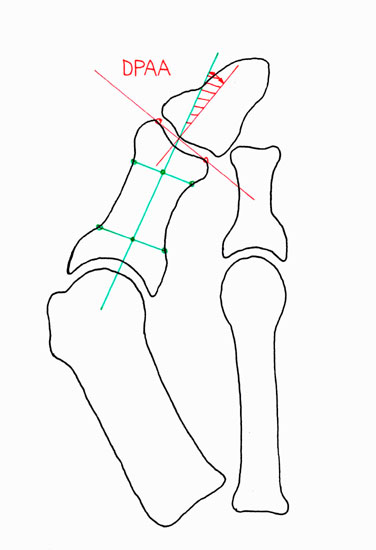

Hallux valgus Operationen gehören zu den am häufigst durchgeführten orthopädischen Eingriffen. Mit dem zunehmenden Wissen um die zugrundeliegenden pathologischen Mechanismen, kann die Anatomie der Fehlstellung präoperativ sehr genau definiert und dadurch eine präzise Planung der notwendigen Korrektur vorgenommen werden. Meistens besteht eine Fehlstellung zwischen dem ersten Metatarsalknochens und der Grundphalanx (HVA; Abb. 3a), welche häufig mit einem erhöhten Winkel zwischen Metatarsale 1 und 2 einhergeht (IMA; Abb. 3a). Seltener besteht eine Hallux valgus Fehlstellung aufgrund einer fehlgestellten distalen Gelenksfläche des Metatarsalknochens (DMAA; Abb. 3b). Die valgische Deformität der Grundphalanx mit veränderten Gelenksflächenwinkeln wird als Hallux valgus interphalangeus bezeichnet (PPAA, DPAA; Abb. 3 c-d). Die Fehlstellung wird normalerweise am Ort der Fehlstellung korrigiert. Im Rahmen der Hallux valgus Korrektur wird bei bis zu 50% der Patienten zusätzlich zur Metatarsale-Osteotomie eine Akin-Osteotomie angeschlossen 12. Eine isolierte Akin-Osteotomie ist nur in der Minderzahl der Fälle das Operationsverfahren der Wahl.

• Beurteilung des proximalen Gelenkflächenwinkels der Grundphalanx (Proximal Phalangeal Articular Angle, PPAA) sowie des distalen Gelenkflächenwinkels der Grundphalanx (Distal Phalangeal Articular Angle, DPAA) 56 (Abb. 3c und 3d).

• Bestimmung des ersten Intermetatarsalwinkels (IMA, Abb. 3a), des Hallux valgus Winkels (HVA, Abb. 3a), des distalen metatarsalen Gelenskflächenwinkels (Distal Metatarsal Articular Angle, DMAA, Abb. 3b) 7. Möglicherweise muss die Akin-Osteotomie mit weiteren Eingriffen kombiniert werden (z.B.: retrokapitale Osteotomie oder andere metatarsale Osteotomie; Arthrodese).